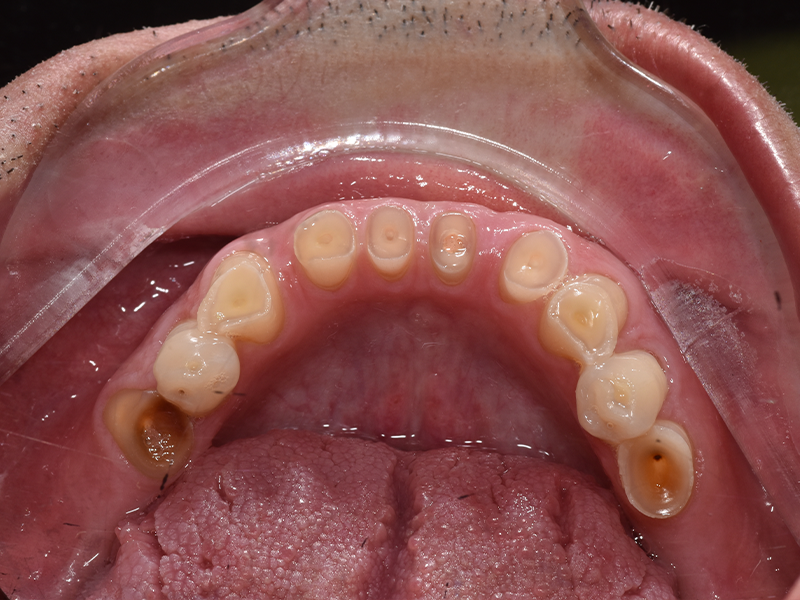

Salvatore, 48 anni, è arrivato nel nostro studio con una storia particolare: per oltre vent’anni aveva bevuto coca cola ogni giorno. Il risultato era evidente: denti fortemente consumati, molari mancanti, difficoltà a masticare e a sorridere. La moglie stessa, preoccupata per lui, ci ha chiesto di intervenire al più presto.

PRIMA